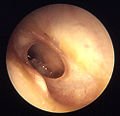

Otitis media with effusion (OME), also called serous or secretory otitis media (SOM), is simply a collection of fluid that occurs within the middle ear space as a result of the negative pressure produced by altered Eustachian tube function. This can occur purely from a viral URI, with no pain or bacterial infection, or it can precede and/or follow acute bacterial otitis media. Fluid in the middle ear sometimes causes conductive hearing impairment, but only when it interferes with the normal vibration of the eardrum by sound waves. Over weeks and months, middle ear fluid can become very thick and glue-like (thus the name glue ear), which increases the likelihood of its causing conductive hearing impairment. Early-onset OME is associated with feeding while lying down and early entry into group child care, while parental smoking, a short period of breastfeeding and greater amounts of time spent in group child care increased the duration of OME in the first two years of life.[1]

In chronic cases or with effusions present for months, surgery is sometimes performed by an otolaryngologist (ear, nose, and throat specialist) or by an otologist (ear specialist), to insert a grommet (called a “tympanostomy tube”) into the eardrum to allow air to pass through into the middle ear, and thus release any pressure buildup and help clear excess fluid within.